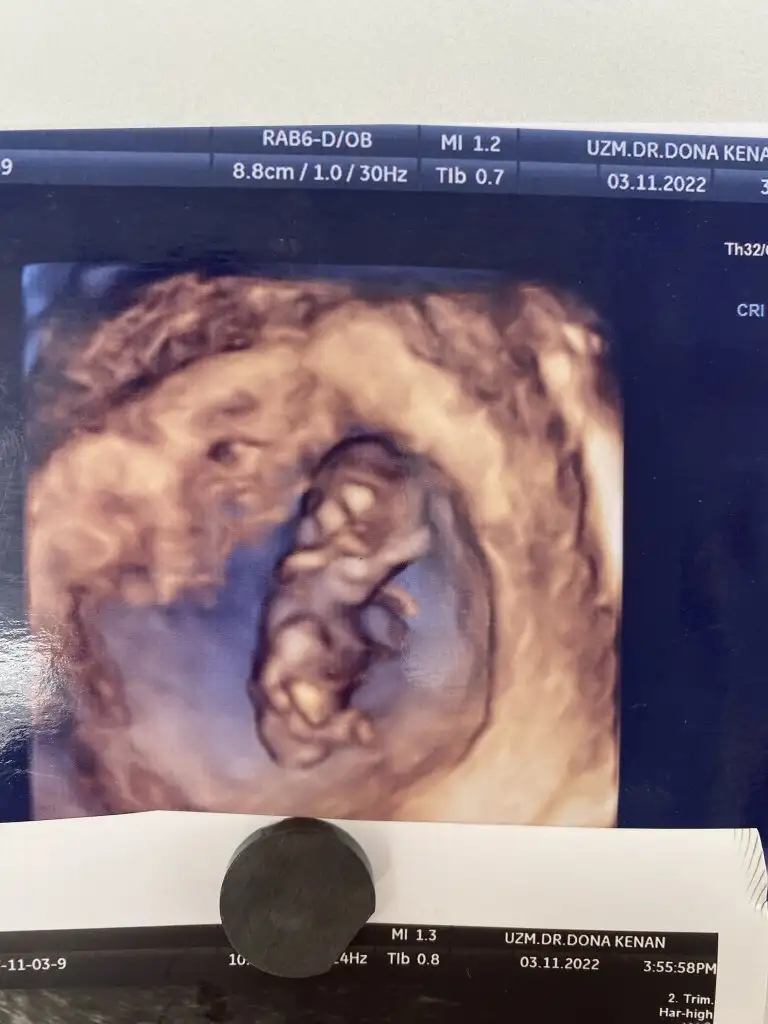

Bana da tahminde bulanbilri misiniz 😍 birinde 9 haftalık birinde 13 haftalık😍

Eklentiler

• IMG-20221130-WA0004.webp

IMG-20221130-WA0004.webp

16,2 KB · Görüntüleme: 107

• IMG-20221111-WA0000.webp

IMG-20221111-WA0000.webp

13,4 KB · Görüntüleme: 116